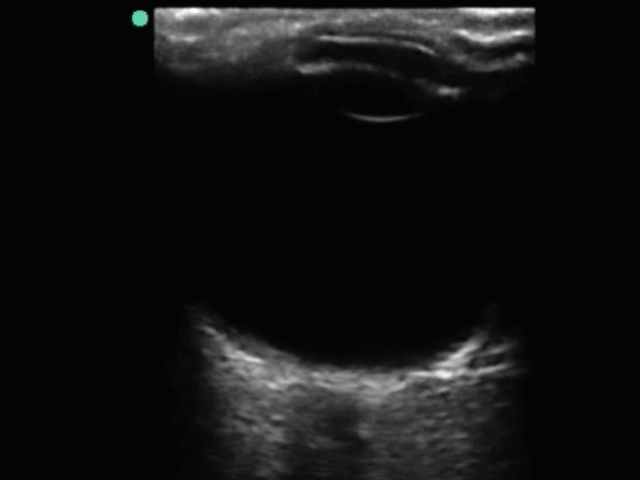

眼部视神经鞘 1 图像